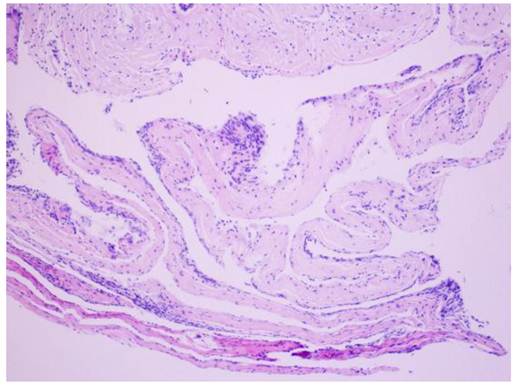

The postoperative symptoms were slightly improved compared to pre-surgery. The results of pathological examination showed that the wall of the cyst was composed of fibrous tissue but without epithelial cells; the diagnosis of arachnoid cyst was made (Figure 2). During three months of follow-up, the condition of this patient continued to improve with normal urination and bowel function and good daily self-management. Physical examinations showed that superficial sensation was gradually diminished and muscle power of upper and lower limbs increased to grade V. Tendon reflex was normal, however, there was no improvement in muscle wasting. MRI re-examination showed that the arachnoid cyst still remained, however, its size appeared slightly smaller than that before surgery. Although the compression on the cerebellar tonsil, pons and cervical spinal cord was reduced, the size of the syrinx was still the same as before surgery (Figure 3).

Figure 2

Results of pathology. H&E staining showing fibrous tissue on the wall of the cyst, and no epithelial cells were observed; arachnoid cyst was diagnosed. Magnification: ×200.